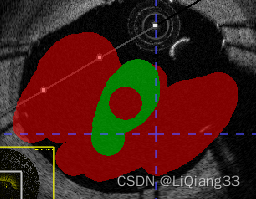

paint over续:使用Active Label=Label1; paint Over=Clear Label标注时,只允许对没有标注的区域标注,如图,同样的,如果paint over=Label1(red), active label = label3则蓝色只能在红色上标注

- 使用画笔工具进行涂画,选择不同的大小进行边界以及内容的填充,选择边界自适应填充可以根据不同的CT值,来填充不同的区域

- 最终的效果